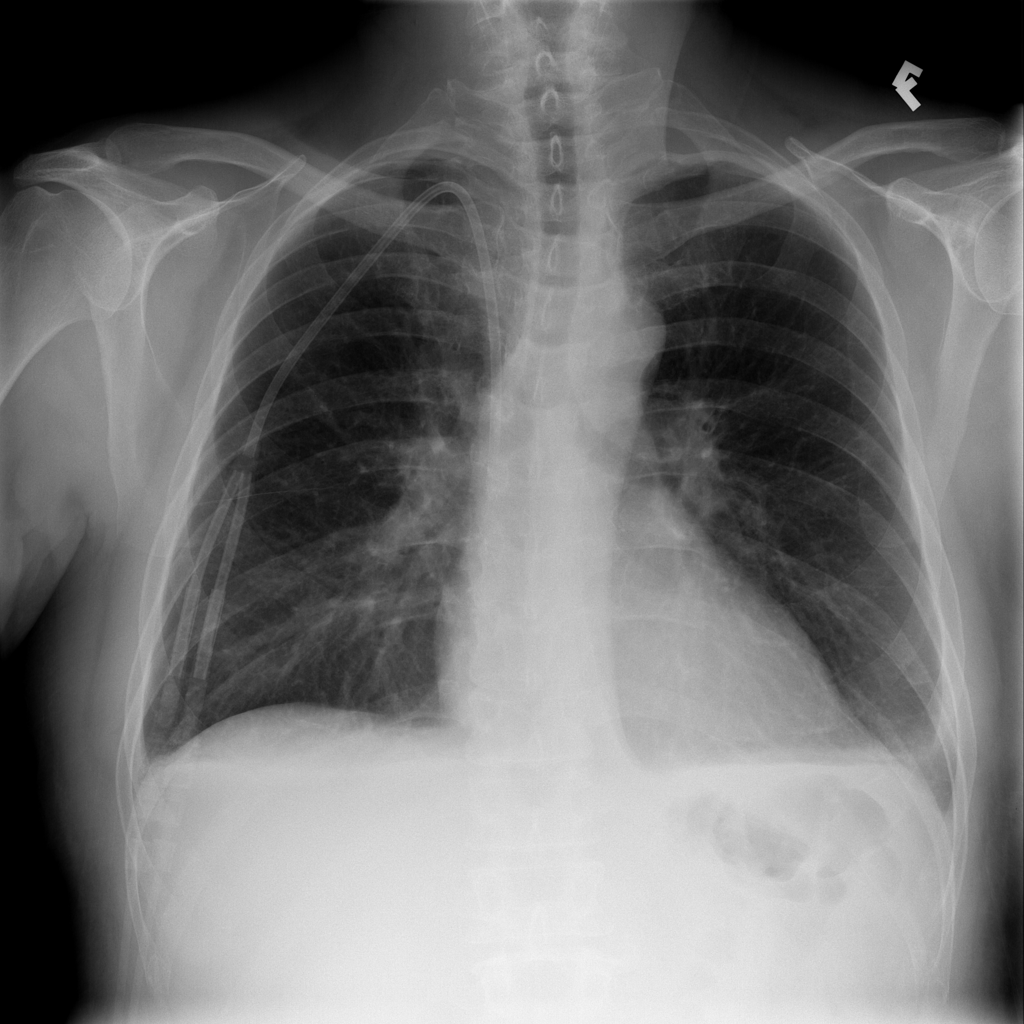

Pleural Effusion

Pleural effusion means extra fluid has collected around the lung in the pleural space. It can happen with heart problems, infection, inflammation, or other underlying conditions.

Showing up to 90 reference images for Effusion.

PAT-40F9 · IMG-004Effusion

PAT-40F9 · IMG-004

PA